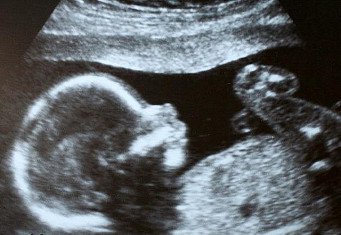

Узи))) 32 неделька!)))

Мы сходили на УЗИ) сказали,что у меня Дочка

Вот такая у меня доча